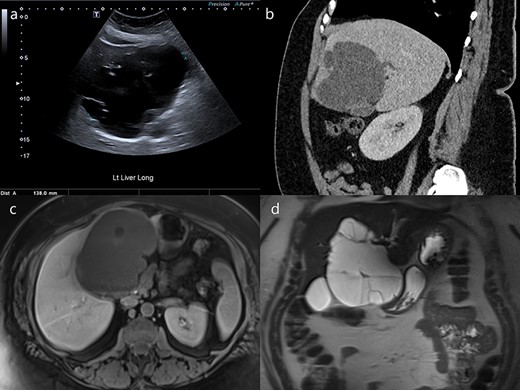

A 50-year-old woman was referred to our institution with a large complex left liver lobe cyst. She had 3 months of epigastric and right hypochondrial pain, associated with nausea and anorexia. Ultrasound had revealed a large, well-defined septated cystic mass in the left lobe measuring up to a maximum diameter of 140 mm (Fig. 1a). Her laboratory data at the time showed deranged liver function tests, with alkaline phosphatase of 472 IU/L, gamma-glutamyl transpeptidase of 1147 IU/L, alanine aminotransferase of 121 IU/L and aspartate aminotransferase of 86 IU/L. The bilirubin was normal at 7 μmol/L, and she had negative hepatitis and hydatid serology.

Ultrasound, CT and MRI imaging of the cyst. (a) Ultrasound detected a septated cyst measuring up to 140 mm in diameter. (b) Intrahepatic bile duct dilatation was demonstrated on CT (sagittal). The cyst was (c) hypointense on T1-weighted images (axial) and (d) hyperintense on T2-weighted images (coronal).

Subsequent abdominal computed tomography (CT) demonstrated the large exophytic multi-septated cyst predominantly within segment IV. It had lobulated margins and thin intrinsic septations with subtle post-contrast enhancement, but no enhancing mural nodule or intrinsic calcification. Additionally, there was mild dilatation of the left liver lobe bile ducts, and displacement of the left and right portal veins due to mass effect (Fig. 1b). Magnetic resonance imaging (MRI) of the liver with cholangiopancreatography confirmed an intrahepatic biliary dilatation more pronounced on the left. The cyst contents were homogenously T1 hypointense and T2 hyperintense (Fig. 1c and d).